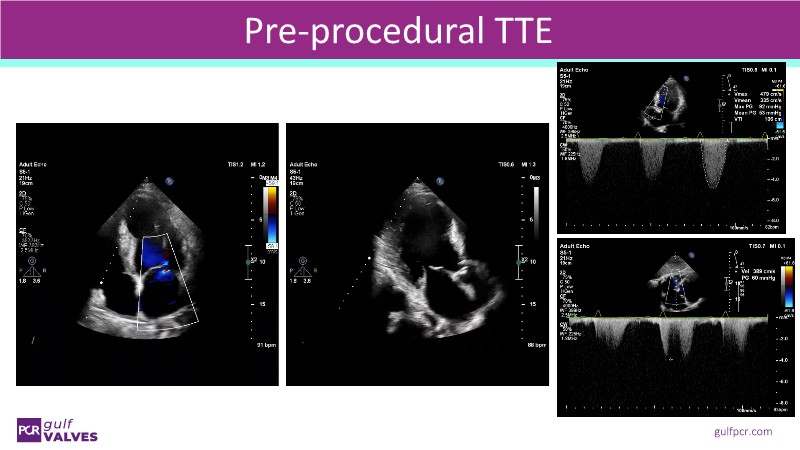

Join this comprehensive session to explore the Myval transcatheter heart valve series, featuring the latest clinical updates from two large randomized controlled trials—Landmark and Compare TAVI. Learn from real-world experiences, including recorded cases, and understand how these innovations translate to complex patient demographics in daily TAVI practice.